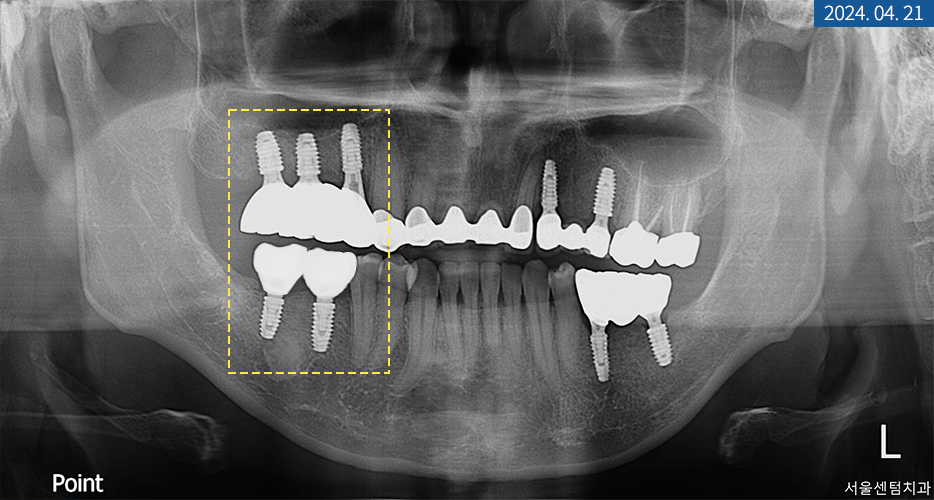

2개월이 더 지나고 나서

잇몸이 둥글게 완성되어

다른 곳과 동일한 방식으로 코핑 연결 후

모양을 본뜨고 기공소에 의뢰했습니다.

도착한 맞춤 브릿지를 씌워드리고 나서

마무리로 치근단 사진 촬영을 해서

주위염은 없는지 체크했습니다.

전체 브릿지 임플란트 완성 후 교합 측정 시

상하악이 알맞게 다물렸으며

내구성 좋은 지르코니아 보철물을 수복했기 때문에

자연치와 조화롭게 어울림은 물론

단단한 식품도 저작할 수 있는 강도를

회복하시게 되었습니다.

마무리 후 시간을 두고

상태 체크를 하는 것이 중요하기에

한 달 동안 사용해 보시라는 안내를 드렸습니다.

그렇게 한 달 후 재방문하신 날짜에 검사를 해보니

뿌리와 치관 주변 등에

아무런 이상 없이 잘 사용하고 계셨습니다.